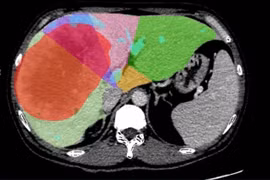

Bệnh viện Trung ương Quân đội 108 đã phẫu thuật nội soi cắt khối u máu gan trái kích thước lớn cho nữ bệnh nhân 46 tuổi.

Đau tức vùng bụng, phát hiện u gan khổng lồ 18,6 cm, phải cắt 2 lần mới hết

Thực hiện thành công Kỹ thuật cắt gan hai giai đoạn để điều trị khối u gan khổng lồ mở ra cơ hội điều trị triệt để, an toàn cho bệnh nhân u gan giai đoạn muộn.